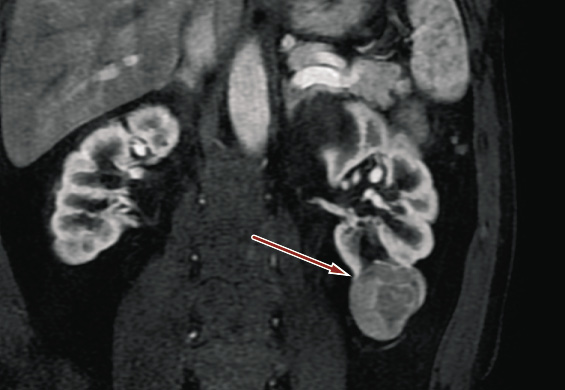

A 54-year-old Caucasian man was admitted to our Urology Clinic due to incidentally detected renal masses on the left side. His past medical history showed hypertension and hypercholesterolemia. He had no past surgical history. His renal functions and glomerular filtration rate were normal. Contrast-Enhanced Computed Tomography (CECT) revealed multi-focal hypodense renal masses and contrast enhancement. The features of the masses were suggestive of multiple renal cell carcinoma without dissemination (Figures 1 and 2).

Figure 1. Intravenous contrast abdominal computed tomography showing a contrast-enhancing 45 mm-diameter solid lesion (red arrow) in the left kidney.

Tumor masses were located in the upper pole, middle renal, and in the lower pole of the kidney. Pre-operative risk in our institution was defined using PADUA and RENAL score. The lesion in the upper pole had a maximum diameter of 20 mm and had no communication with the urinary tract. PADUA score was 7p and RENAL score was 5a. The lesion located on the middle line had maximum diameter of 25 mm and was closed with the urinary tract, in fact PADUA score was 9a and RENAL score was 7a. The lower one had maximum diameter of 45 mm and reached urinary tract as well. Because of the size, it had PADUA score = 9a and RENAL score = 10a. According to TMN classification, the patient was classified as T2bN0M0 clinical stage. The Charlson comorbidity score was 0.